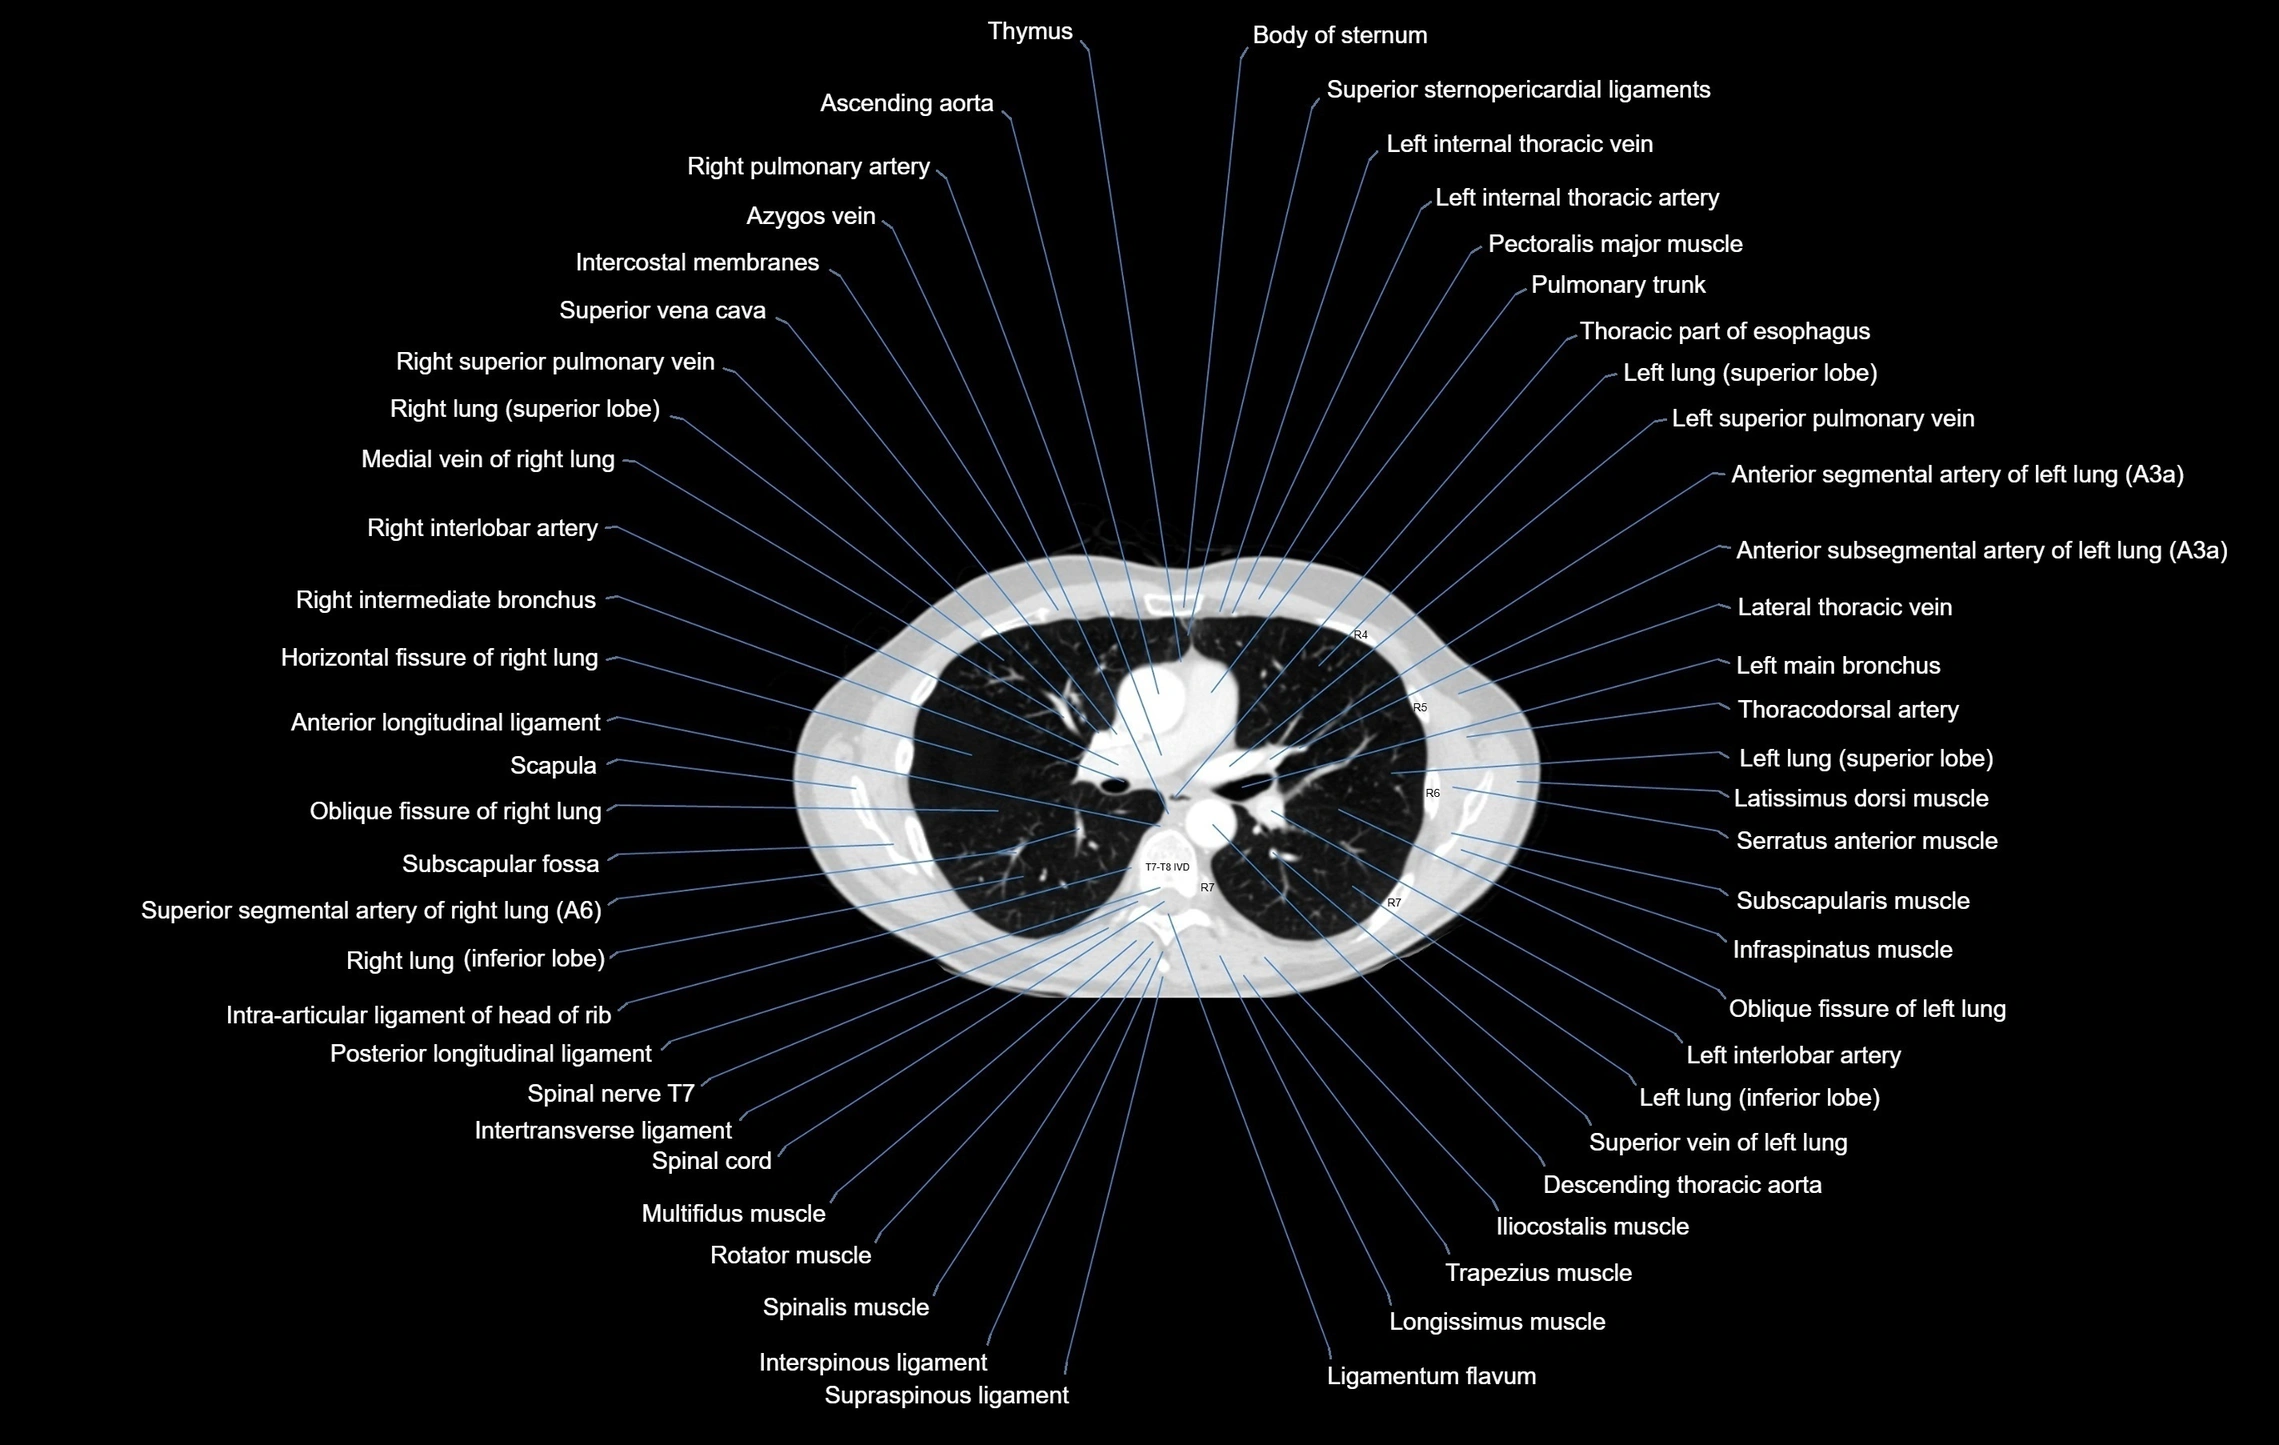

- T (Thoracic spine)